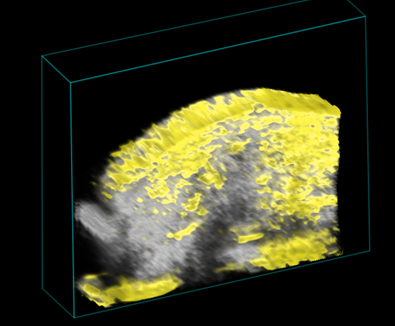

Using the Vevo F2 Lazr-X system, we monitor and quantify tumors in rodent models with high-resolution ultrasound and photoacoustic imaging. Our capabilities include:

- Morphological assessment: Tumor size and volume via 2D/3D imaging.

- Photoacoustic imaging: Measurement of oxygen saturation and hemoglobin within tumors.

- Early detection: Photoacoustic contrast agents (wavelength 680–970 nm) for sensitive identification of small or early-stage tumors.

This comprehensive approach supports studies on tumor growth, angiogenesis, and therapy response.